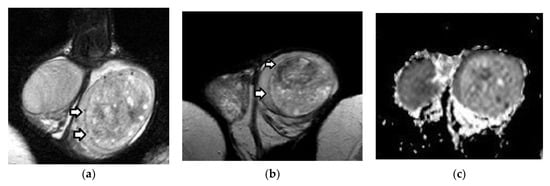

3.1. MRI Findings of TGCTs